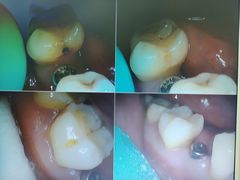

• 牙博士口腔品牌连锁(杨浦店)

• -牙博士口腔品牌连锁(杨浦店)